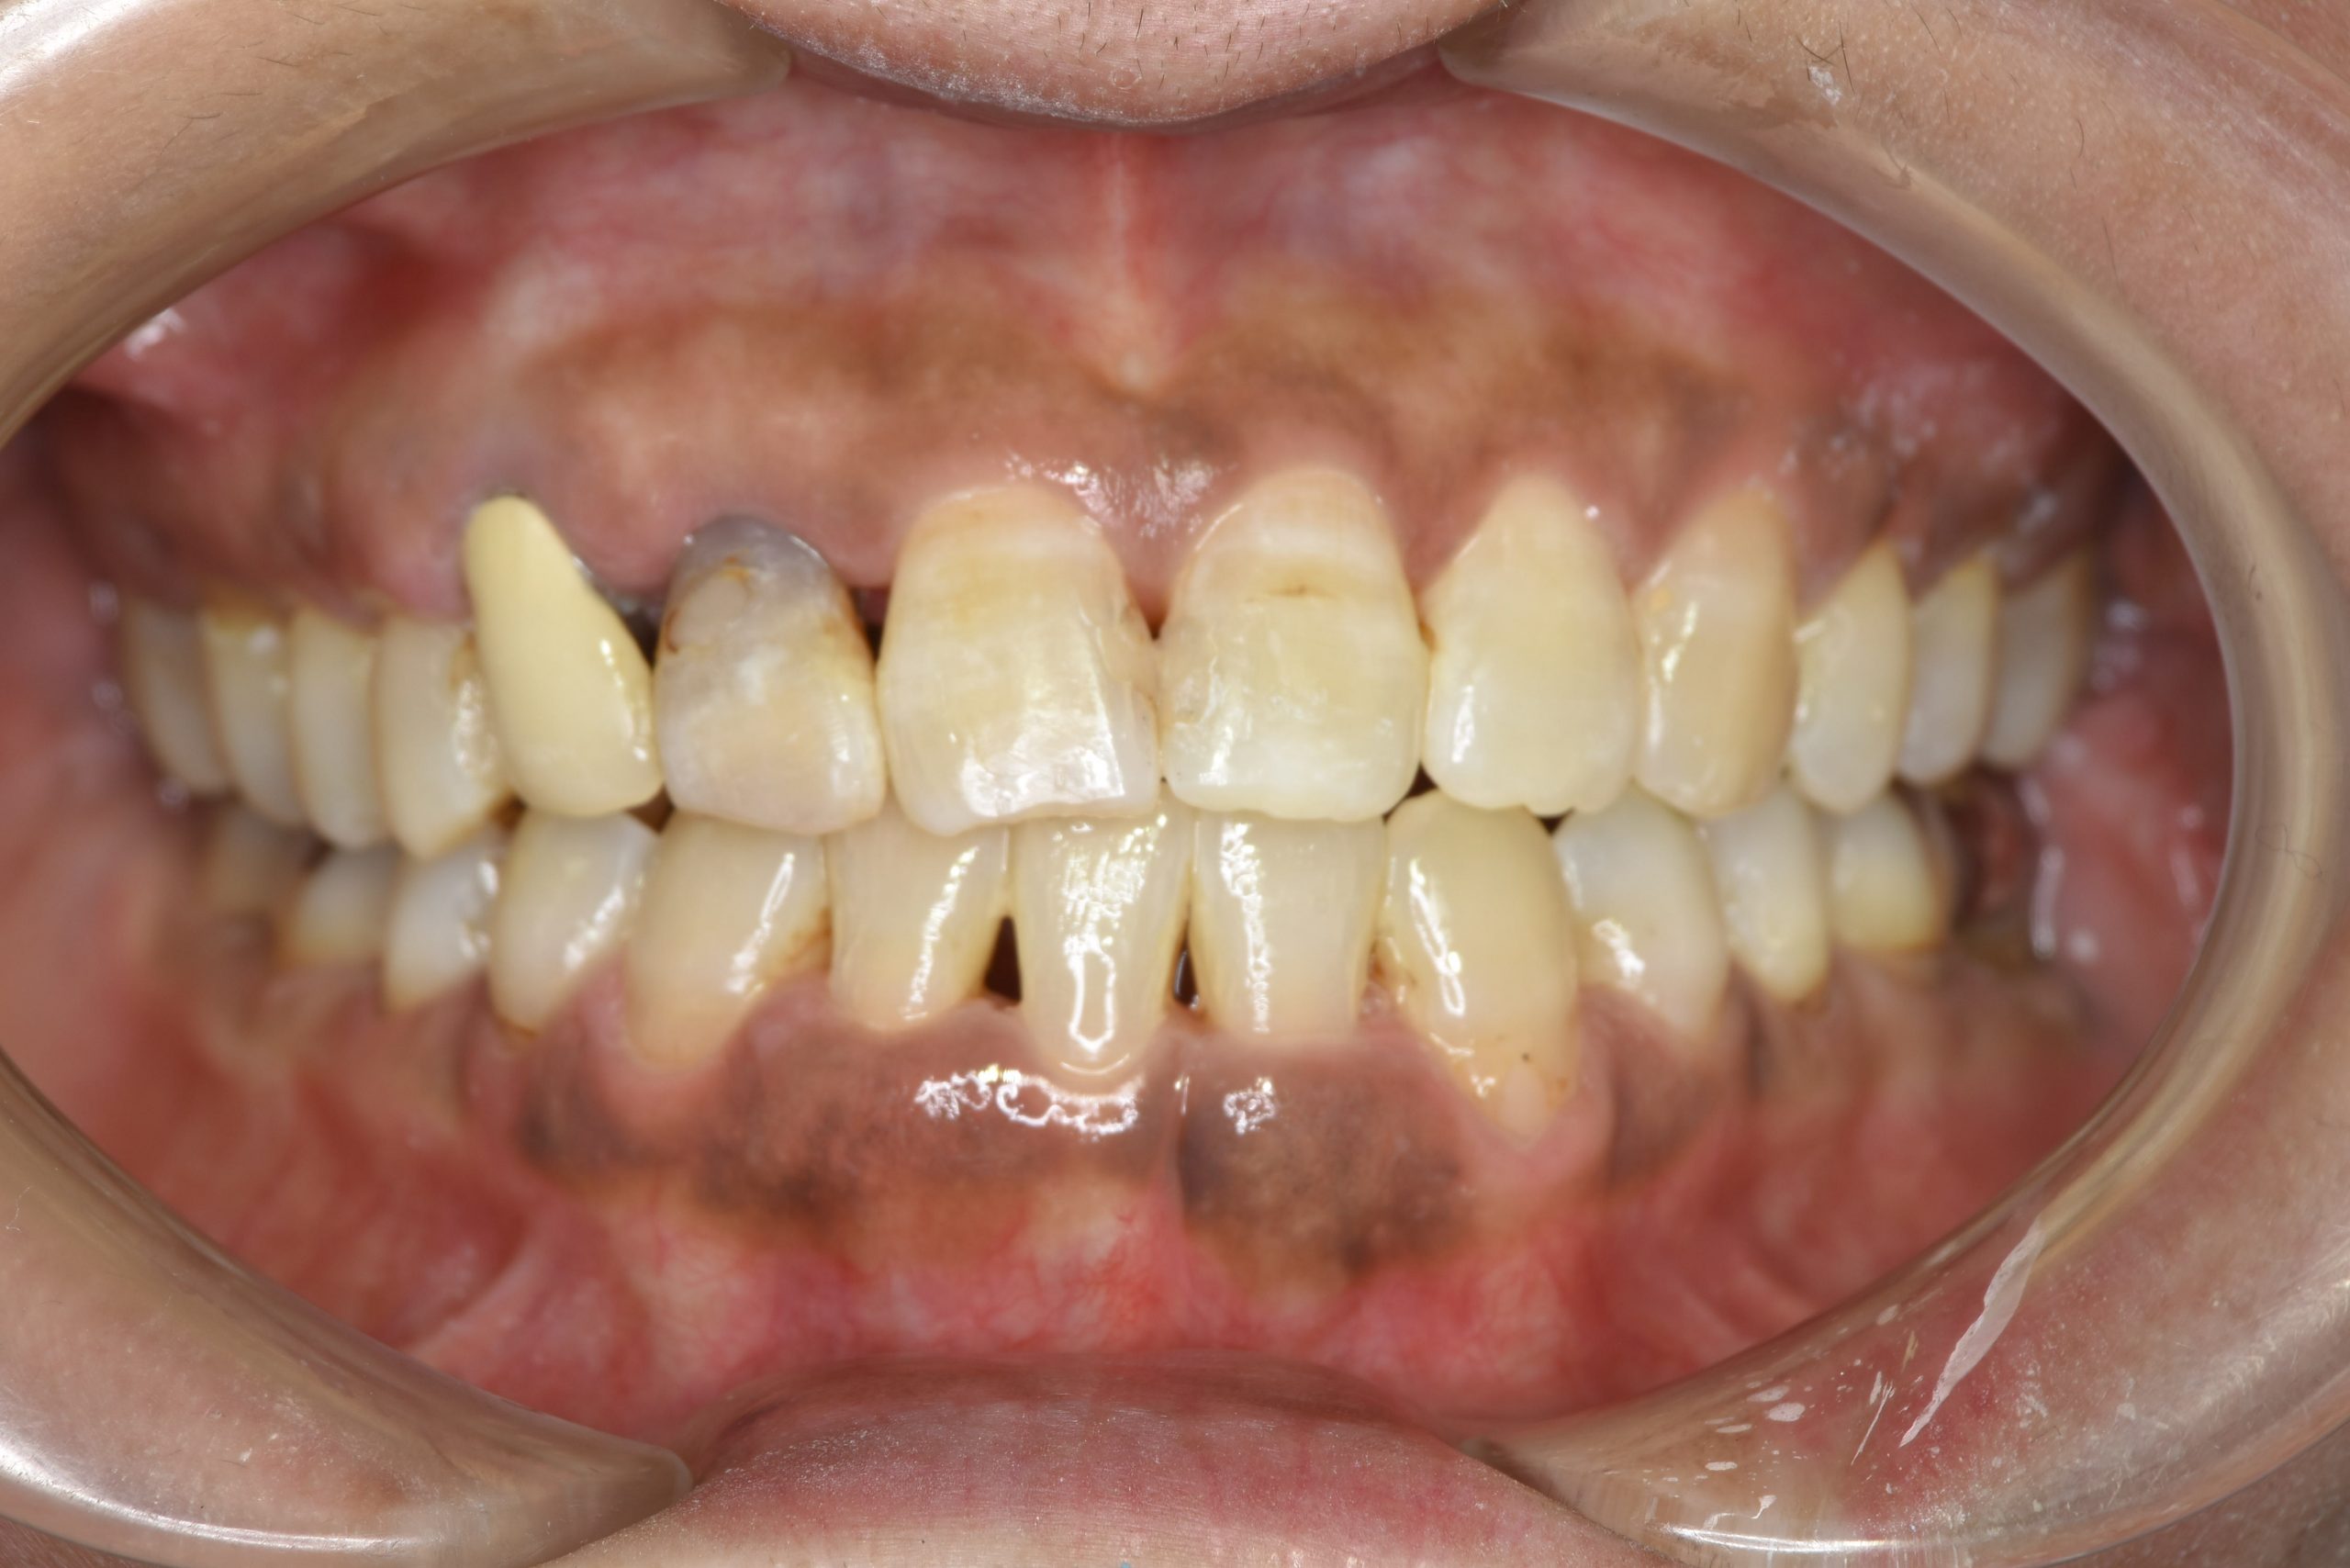

ビフォー

ワイヤー矯正治療|症例_588

主訴 かみ合わせ ※抜歯あり

施術内容 MSEと下顎リンガルアーチを用いて上下顎骨を拡大した。

その後下顎前歯を1本抜歯してマルチブラケット装置を用いて

歯牙を配列し良好な咬合を獲得した。側貌は改善した。